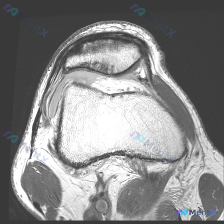

膝关节MRI提示软骨异常,这份分析思路帮你理清方向

刚整理完一份膝关节MRI读片病例,核心问题是发现软骨异常,把完整的分析思路分享给大家。

本次影像为膝关节冠状位T2加权脂肪抑制序列MRI,已经清晰显示膝关节主要结构,脂肪抑制序列很好突出了水肿、积液等异常高信号。

- 半月板:内侧半月板体部形态完整,内部可见异常高信号,未贯穿上下关节面;外侧半月板结构连续,无明显异常信号。

- 韧带:前交叉韧带正常束状低信号结构模糊,代之以弥漫高信号,连续性难以辨认,符合撕裂表现;内侧副韧带结构连续,无明显异常;外侧副韧带显影局限,未见明确断裂。

- 骨结构:股骨外侧髁、胫骨外侧平台均可见片状高信号,呈现典型的对吻性骨挫伤/骨髓水肿分布。

- 关节腔:可见较多高信号积液影,分布于髁间窝及侧隐窝,提示关节腔积液。